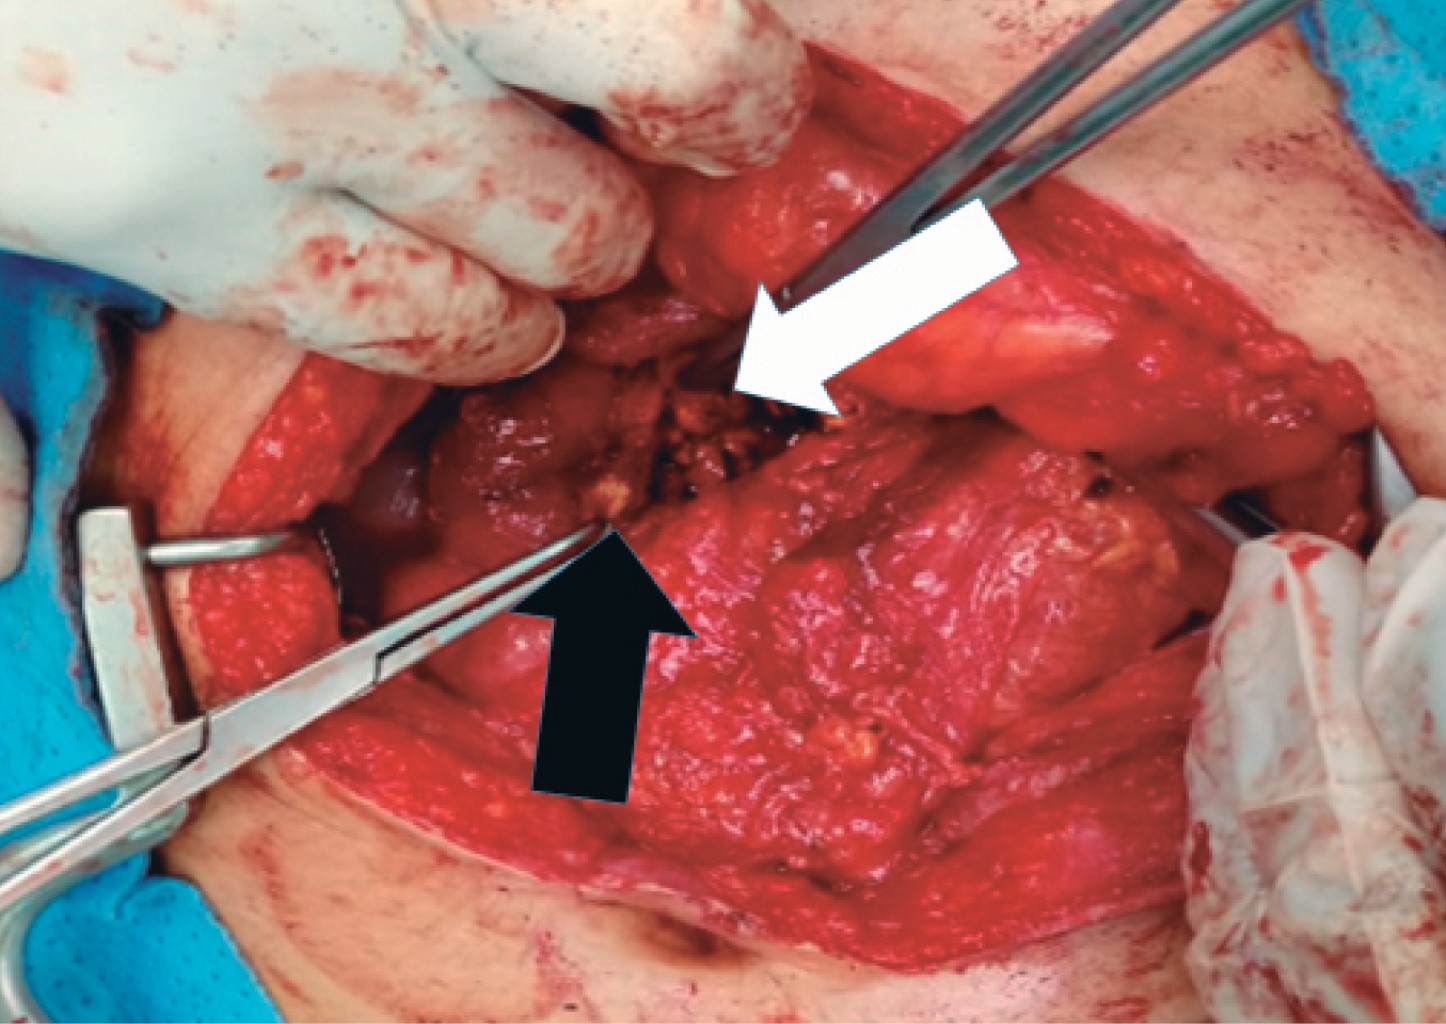

The patient underwent exploratory laparotomy where a tumor mass of approximately 6 × 8 cm was identified at the level of the head of the pancreas attached to the second portion of the duodenum, so we proceeded to perform enucleation by dissection of the second portion of the duodenum and the trans-pancreatic portion involving the main pancreatic duct, The duodenum was then splinted with a No. 12 Nelaton, which was exteriorized through the second portion of the duodenum towards the abdominal wall at the height of the right flank, and fixed with a PDX 3 (polydioxanone) suture (Figures 2, 3 and 4).

The patient had a favorable postoperative period of 33 days. Additional to general measures, broad-spectrum antibiotic therapy was administered corresponding to amikacin 680 mg intravenous every day for 10 days accompanied by imipenem 500 mg every six hours intravenous for 15 days, and then cefalexin 500 mg orally every eight hours for seven days. After discharge, cefuroxime 500 mg orally every 12 hours for five days were given. Total parenteral nutrition was started on the third postoperative day and maintained for 10 days. On the seventh postoperative day, a strict liquid diet was started which was then progressed to a soft diet that was well tolerated. A somatostatin analogue from the beginning of the postoperative period at a rate of 4 µg intravenous every eight hours until discharge was used. A rigorous control of the drain was established, performing daily clamping of the drain for 24 hours and then continuing with control of the fistula to see if there was any fluid arrest or leakage Finally, it was decided to remove the drain (Figure 5).